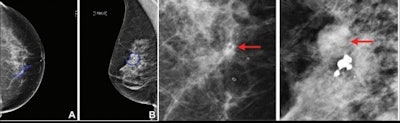

Along with cancer or noncancer classification, the researchers explored whether biopsied lesions detected at mammography could be further classified into more specific subtypes such as DCIS, invasive cancer, high-risk lesions, and benign lesions. The team also investigated whether including clinical characteristics from patients could improve the algorithm's accuracy.

For classifying pathologies, the best-performing algorithms achieved an AUC of 0.76 for DCIS, 0.85 for invasive carcinomas, and 0.82 for benign lesions, respectively. These included both clinical and imaging features in the Israeli training and test sets.